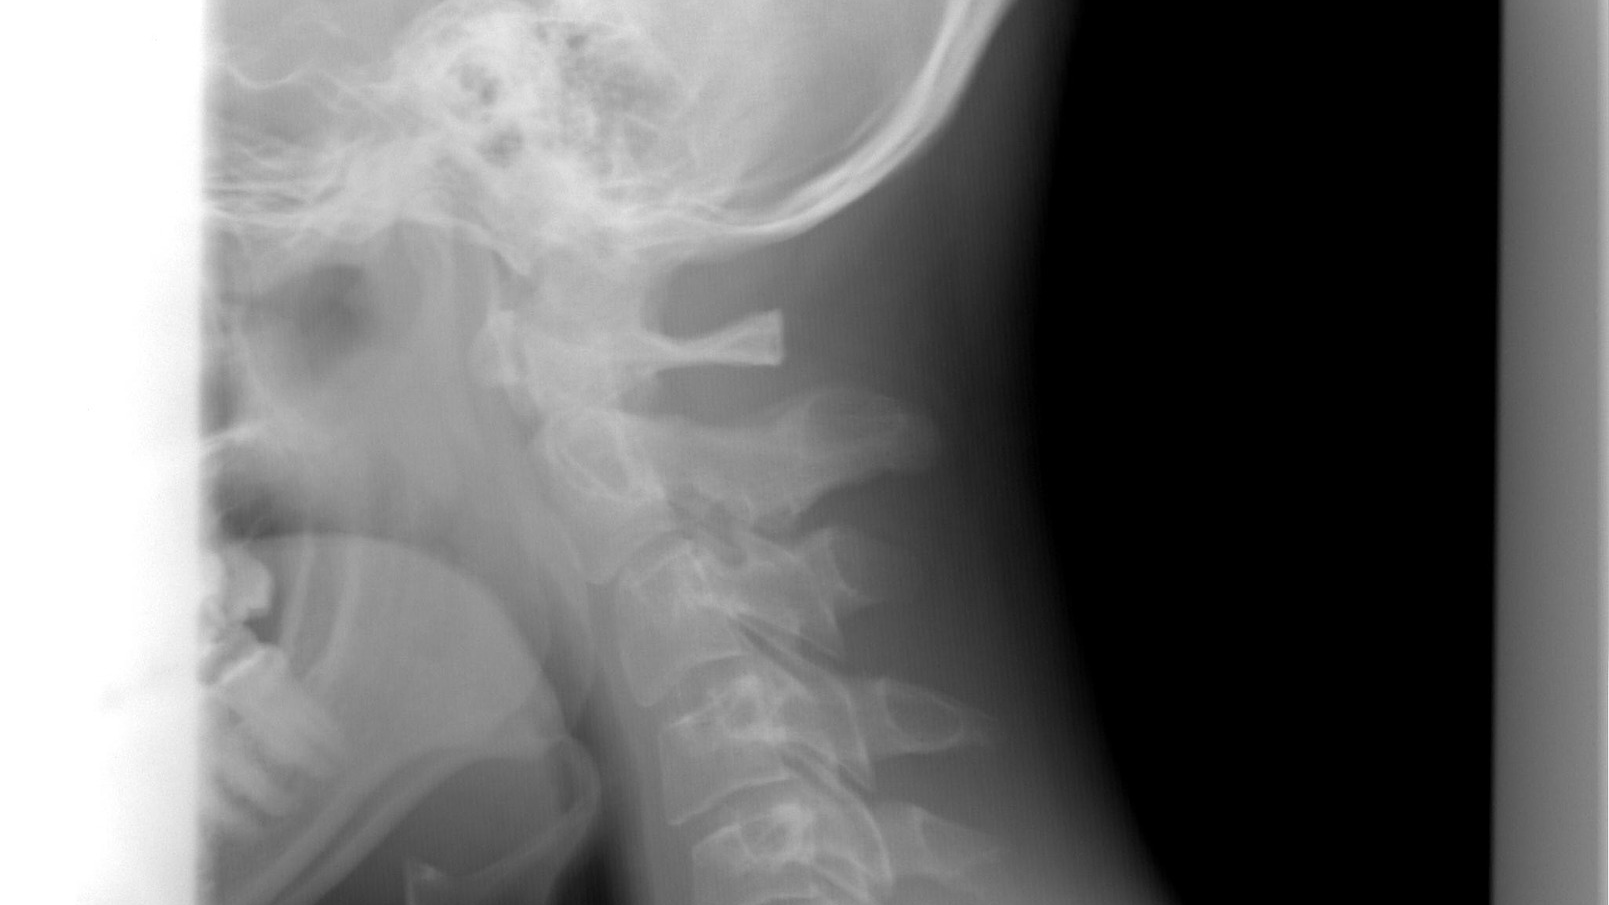

The patient had a quarter-sized hole in his skull base, which separates the brain from the nasal cavity – an unfortunately common problem in patients who undergo surgery in that part of the skull. The hole caused air to build up inside the patient’s cranial cavity, cerebrospinal fluid to leak into the nose, and meningitis, according to a new report in the journal World Neurosurgery.

The Rutgers-led solution took a paramedian forehead flap – an age-old procedure in which a section of skin and muscle is cut away from the forehead and rotated downward, traditionally to reconstruct part of the nose. But for this patient, they used an endoscope to insert the flap of forehead tissue inside the patient’s head through an incision above his nose, then attached it to the skull base where it successfully closed the hole.